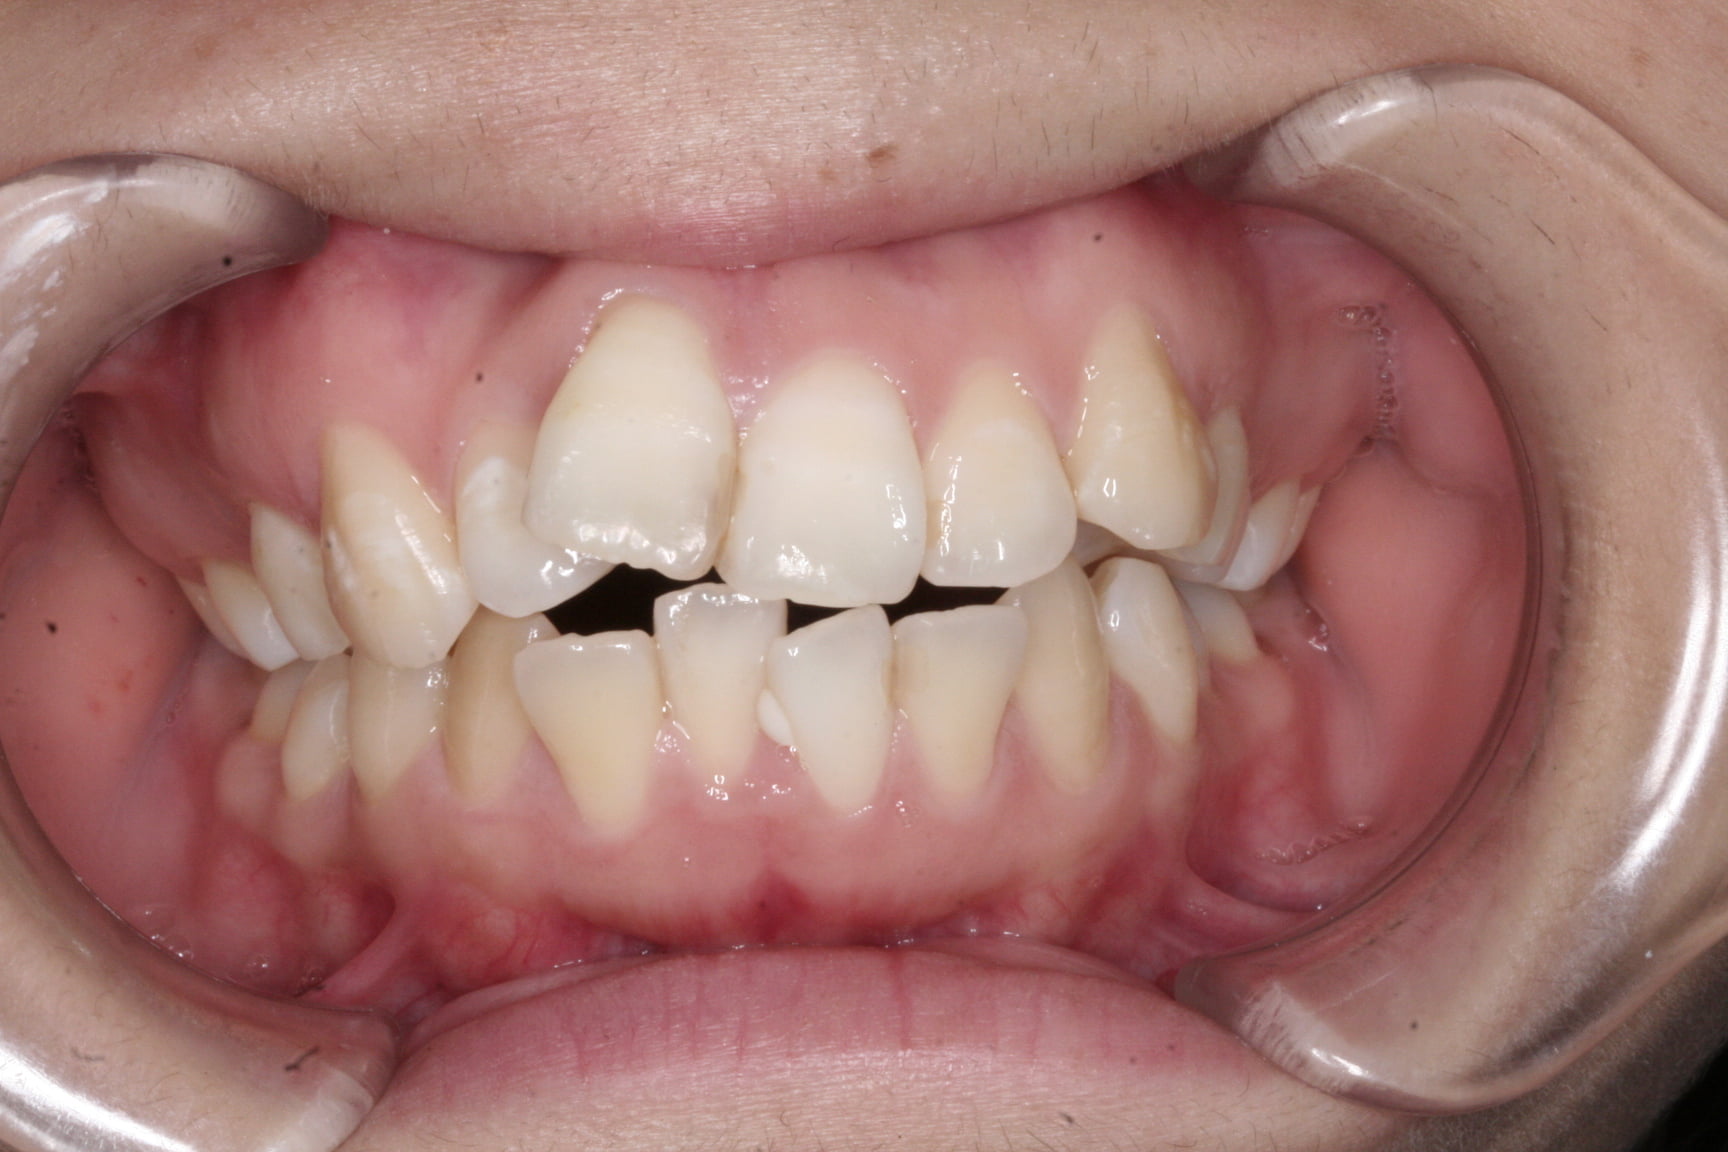

出っ歯を治したい

結婚式までに短期間で改善したい!叢生・出っ歯

年齢層 20代

性別 女性

主訴 【主訴】凸凹を治したい・上の歯が出ている 【診断・症状】叢生・過蓋咬合・骨格性下顎劣成長・骨格性2級咬合

治療費用 ¥1,375,000

治療期間 約2年6か月(30回)

抜歯 抜歯:有(上4,4)

矯正の装置 裏側矯正(舌側矯正)

副作用、リスク 歯肉退縮・歯根吸収・疼痛・咬合の違和感・装置の違和感

症例

Before